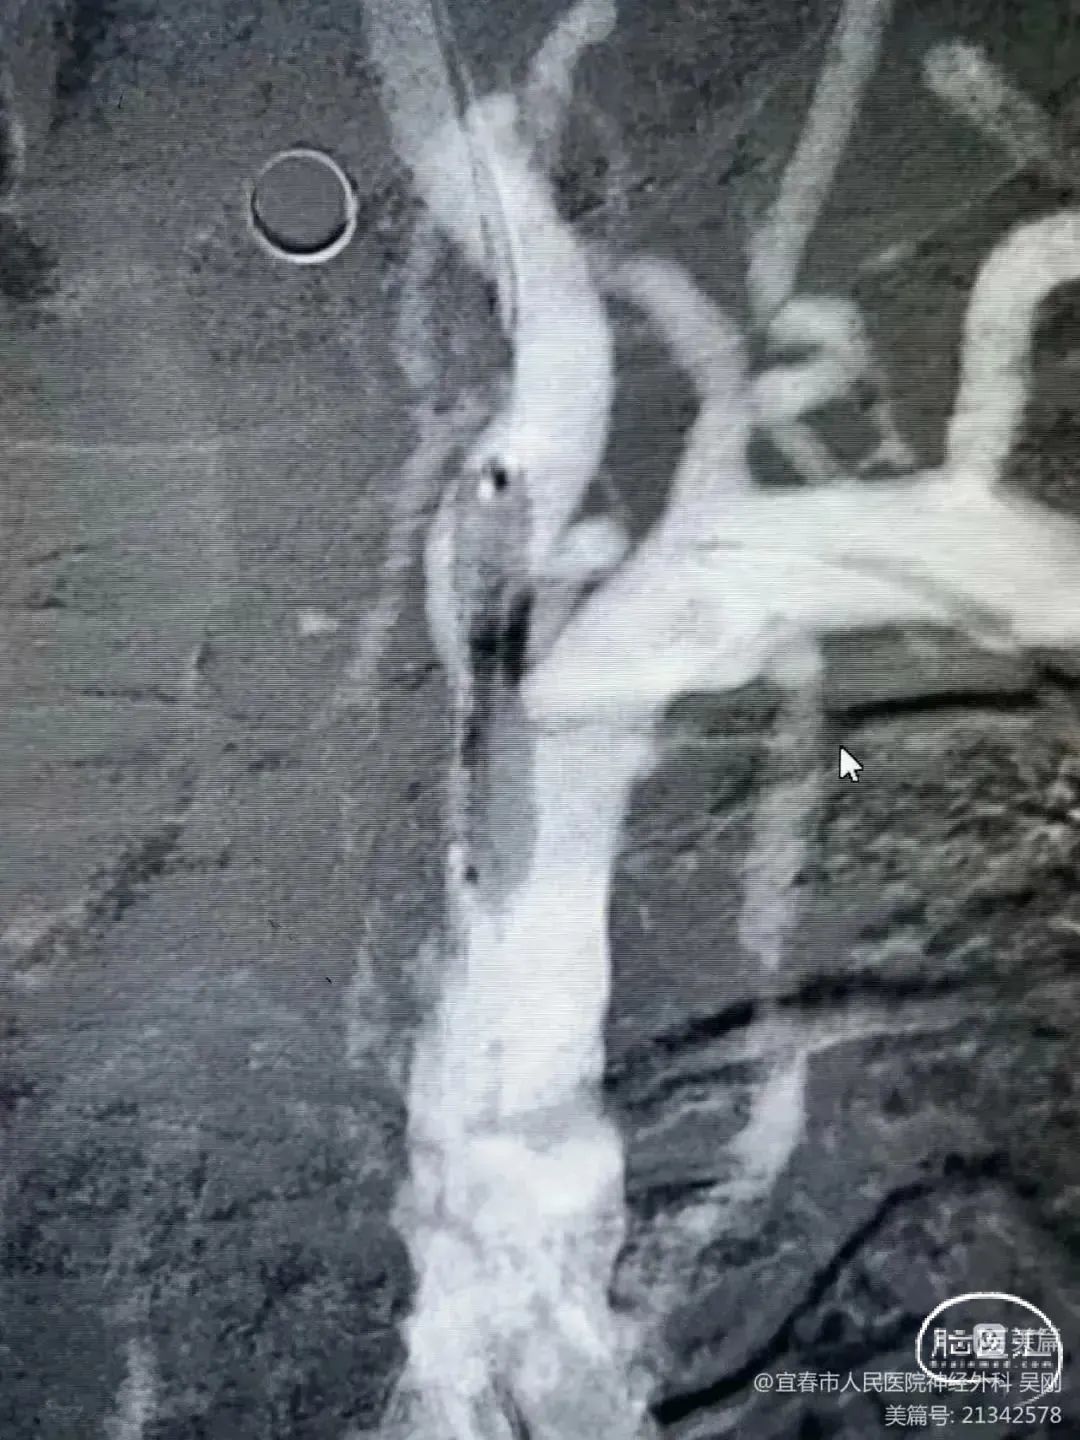

术后造影:

血管再通,前向血流3级。左侧为胚胎型大脑后。

术后CTA:Bridge药物支架形态良好,前向血流良好。

术后半年CTA:Bridge支架形态及贴壁良好,前向血流正常。